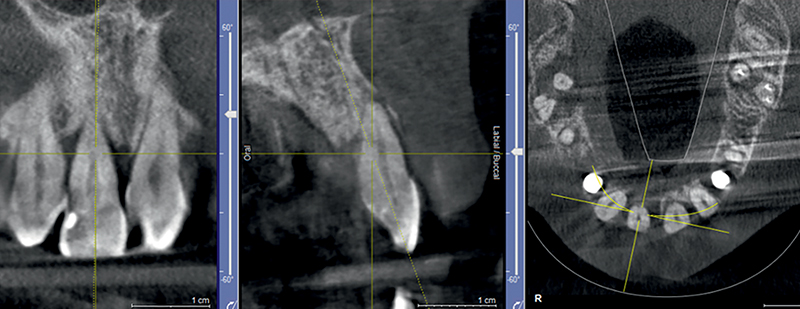

Fig. 12 (caso 3) - Pianificazione implantare con CBCT

Caso 3: Un paziente maschio subiva un trauma durante l'infanzia e si presentava con una fistola associata al dente 11 e un difetto della cresta alveolare vestibolare. Il paziente era sottoposto a posizionamento immediato di un impianto SDS. In questo caso, l'aumento veniva combinato con il prelievo di tessuto connettivo subepiteliale (SCTG) dal palato, attraverso una singola incisione, tunnellizzazione buccale e inserimento dell’innesto. I successivi appuntamenti di follow-up rivelavano il successo della preservazione della cresta alveolare vestibolare, e della guarigione dei tessuti molli attorno all'impianto. L'osteointegrazione avveniva senza problemi e si poteva iniziare la pianificazione della corona definitiva. Questo caso era seguito per 5 anni e anche dopo questo periodo il contorno alveolare era estremamente soddisfacente. La guarigione e la gestione dei tessuti molli erano adeguate, suggerendo come l'applicazione dell'innesto di tessuto connettivo abbia contribuito positivamente al risultato estetico (Fig. 11-17).